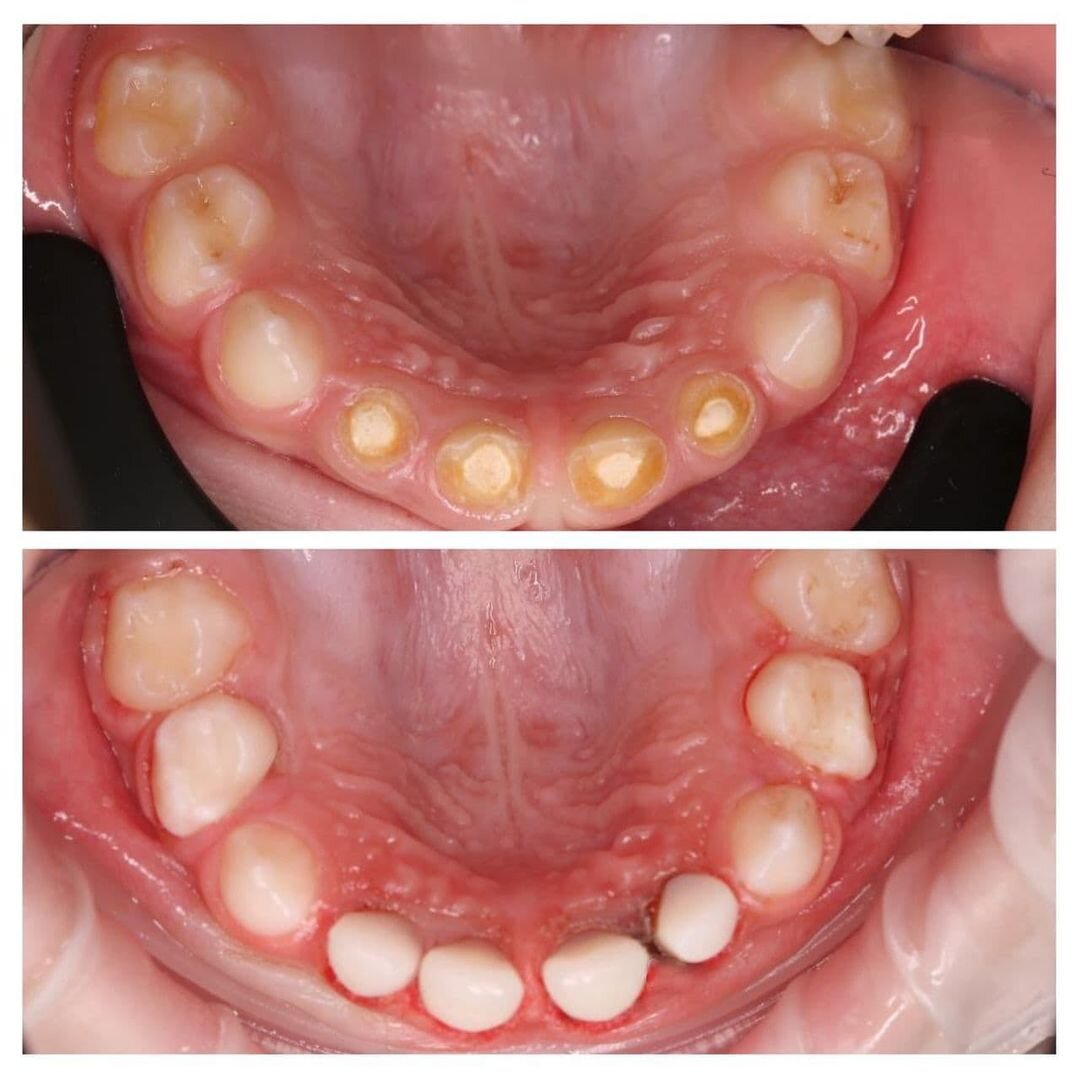

Лечение 16 молочных зубов за одно посещение!

Верхние резцы прорезываются одними из первых и страдают сильнее всего.

Наглядный пример — наш маленький пациент.

Ему всего 2,5 года, а от четырех верхних резцов практически ничего не осталось.

Всё «съел» кариес❗

Кроме резцов пострадали практически все остальные зубы.

К сожалению, у кариеса нет приоритетов — где условия позволяют, там и появляется.

Малыша лечили под наркозом.

А теперь внимание, сколько зубов было поражено?

ШЕСТНАДЦАТЬ!

❗16 зубов вылечила за 4 часа наш детский стоматолог Мария Штельмах!

• Сделано 8 реставрации;

• Вылечен 1 пульпит и 4 кариеса;

• Загерметизированы 3 зуба.